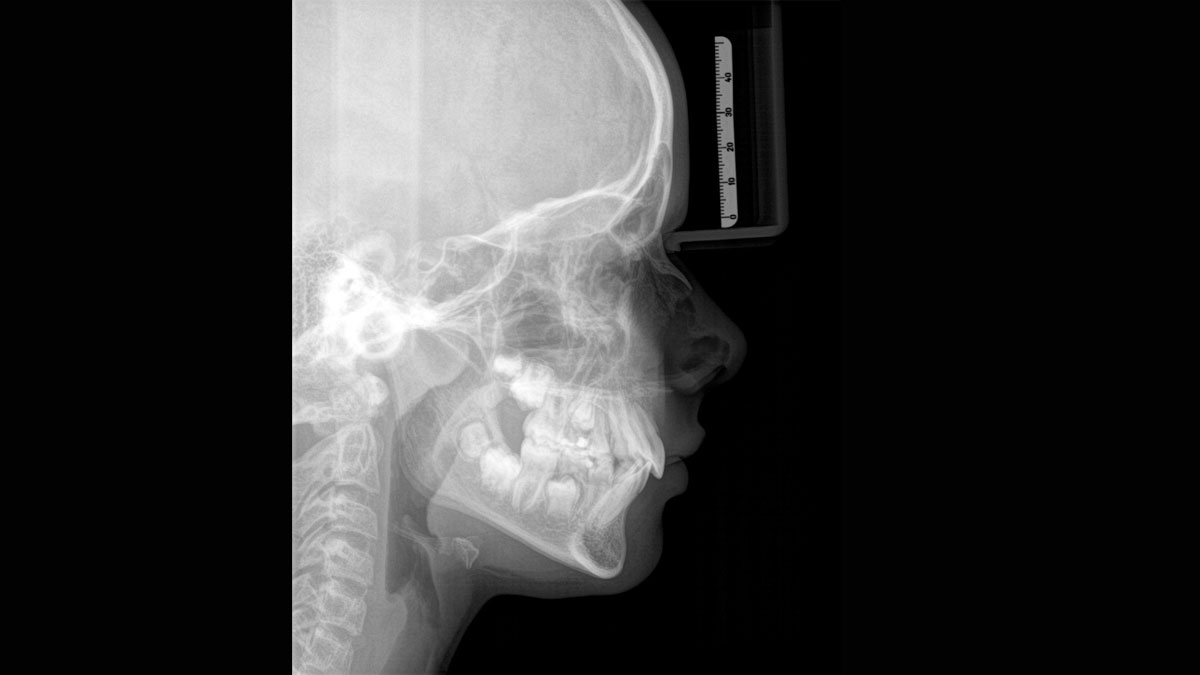

Het hoogwaardige 2D/3D-röntgenapparaat met uitgebreide mogelijkheden voor elke praktijk. Of het nu gaat om een puur 2D-apparaat of een 3D-module, de Orthophos S is een betrouwbare partner die helemaal is geoptimaliseerd voor dagelijkse taken. De CsI Plus-sensor met autofocusfunctie geeft heldere beelden, zelfs in anatomisch moeilijke gevallen. De automatische patiëntpositionering in combinatie met het gepatenteerde occlusale bijtblok maakt een eenvoudige en tijdbesparende patiëntpositionering mogelijk. Voor gebruik in orthodontie is de Orthophos S ook verkrijgbaar met een optionele ceph-arm. Uw praktijk toekomstbestendig houden is voor ons belangrijk en daarom kan de cephalometrische arm op elk moment achteraf worden ingebouwd.

Zelfs in anatomisch moeilijke gevallen met de 2D CsI Plus-sensor met autofocusfunctie.

De juiste focus is cruciaal voor hoogkwalitatieve panoramische röntgenfoto's. Met de autofocusfunctie ontvangt u automatisch een beeld met de best mogelijke scherpte. Dentsply Sirona Imaging-apparaten maken enkele duizenden afzonderlijke beelden in één cyclus en identificeren automatisch de gebieden waar de kaak optimaal is gepositioneerd. Zonder extra handmatige stappen worden deze beelden vervolgens weergegeven in een definitieve scherpe afbeelding.

Slechts enkele delen van het beeld zijn scherp, terwijl andere gebieden wazig zijn.

Het systeem detecteert de relevante gebieden van enkele duizenden afzonderlijke beelden in één cyclus en identificeert automatisch de gebieden waar de kaak optimaal is gepositioneerd.

Scherpe beelden.